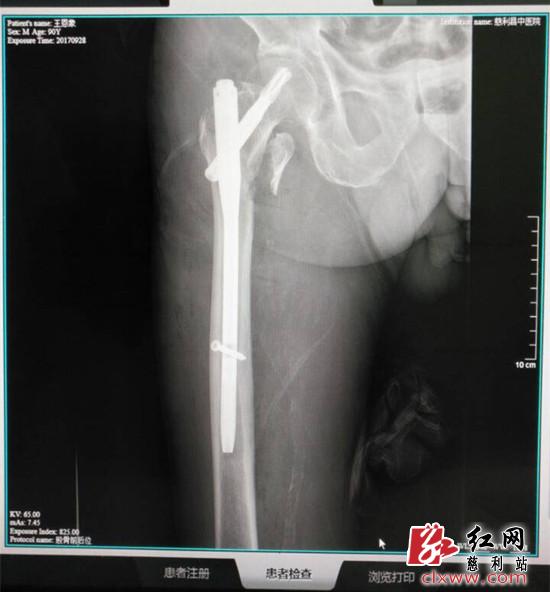

(术后)

由于病人系高龄老人,并且先天性聋哑、老年痴呆,沟通困难、配合度较低,手术风险系数高。但考虑到如果不进行手术,病人将长期卧床不起,还可能继发肺部感染、下肢深静脉血栓等并发症,对老人来说是致命的伤害。经骨科专家讨论后决定为老人实施手术治疗。为保证手术顺利安全,慈利县中医院骨科团队拟定了详细的手术方案和充分的应急准备。9月27日,老人被推进手术室,在麻醉科、心内科、呼吸内科的亲密协作下,历时2小时,手术取得圆满成功。目前老人身体恢复状况很好,加上后期药物治疗、精心护理调护及适当功能锻炼,预计一周后能尝试重新站立行走。